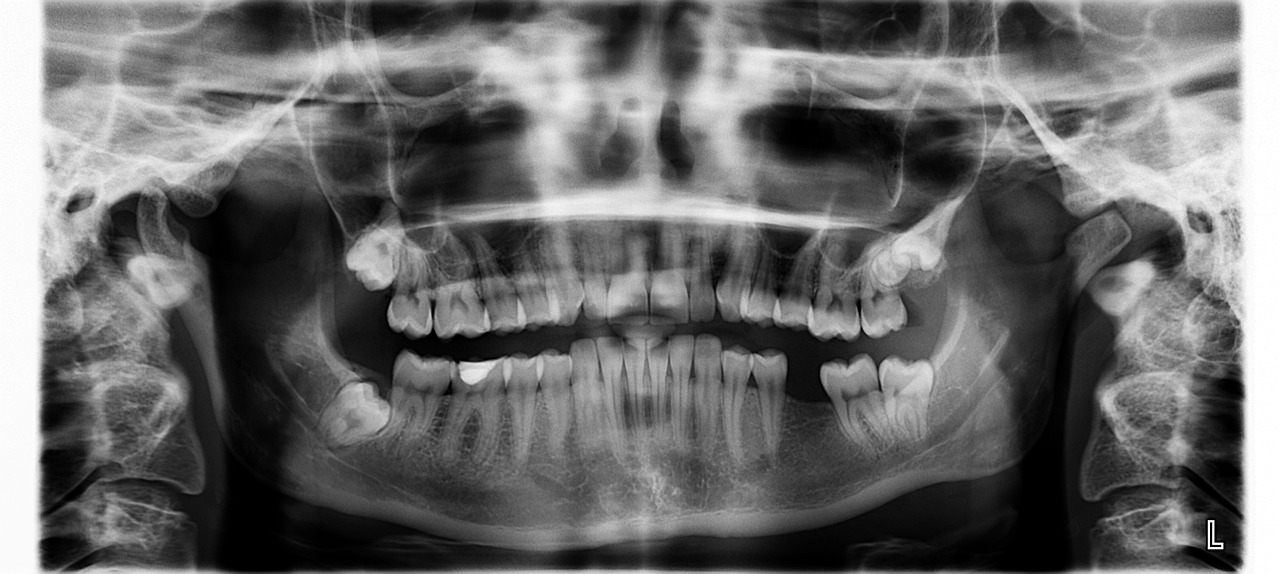

임플란트, 크라운, 레진 등 보존치료 & 보철치료 방법과 치아보험 가입 사례

치아는 한 번 손상되면 자연적으로 회복되지 않기 때문에 치료가 필요할 경우 비용 부담이 큽니다. 특히, 임플란트, 크라운, 레진과 같은 보존치료 및 보철치료는 치료비가 높고 건강보험 적용 범위가 제한적이라 부담이 될 수 있습니다.

이럴 때 치아보험이 있다면 비용 부담을 줄이면서 최적의 치료를 받을 수 있습니다. 이번 글에서는 보존치료 및 보철치료 방법을 비교하고, 실제 치아보험 가입 사례를 통해 가입 시 고려해야 할 점을 알아보겠습니다.